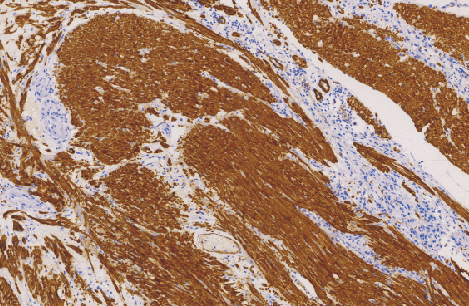

Myosin Heavy Chain (SMMHC)鼠抗人肌球蛋白重链(平滑肌)单克隆抗体

平滑肌肌球蛋白重链主要用于标记血管和内脏平滑肌细胞以及肌上皮细胞,被认为是平滑肌较为特异和可靠地标志,有助于间叶肿瘤的诊断和分类,亦用于乳腺肌上皮细胞的检查,有助于原位癌和浸润癌的区别。

- 阳性部位:胞质

- 适用组织:石蜡切片

- 预处理:热修复